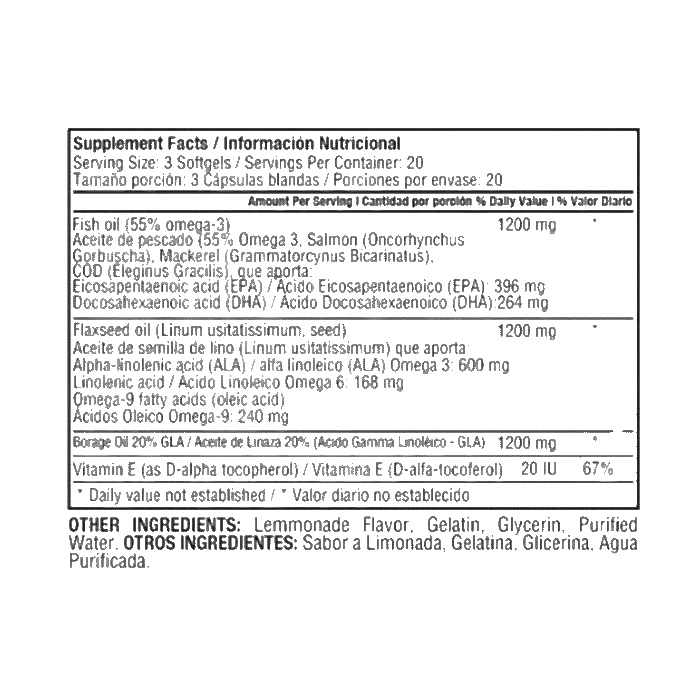

Potente mezcla de ácidos grasos esenciales Omega 3, 6 y 9 con 1200 mg por cápsula. Contribuye a la salud cardiovascular, cerebral y de la piel. Ideal para quienes buscan bienestar integral y nutrición completa en una sola cápsula diaria

El Triple Omega 369 es una combinación esencial de ácidos grasos que apoya funciones vitales del cuerpo. Esta fórmula proporciona los beneficios del Omega 3, 6 y 9, esenciales para mantener una buena salud.

- Apoya la salud cardiovascular y reduce los niveles de colesterol.

- Contribuye al buen funcionamiento del cerebro y la memoria.

- Mejora la salud de la piel, articulaciones y sistema inmunológico.

- Proporciona ácidos grasos esenciales no producidos por el cuerpo.

- Ideal para personas con dietas deficientes en grasas saludables.

Tomar 1 cápsula al día, preferiblemente con una comida.